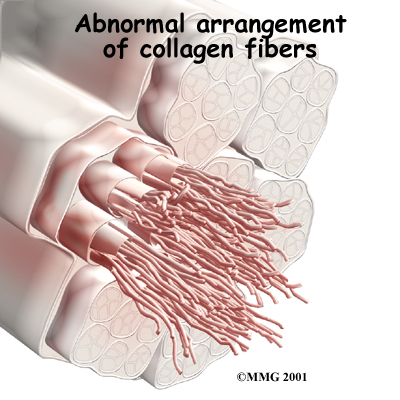

Tendons connect muscle to bone. Tendons are made up of strands of a material called collagen. The collagen strands are lined up in bundles next to each other.

Collagen

Because the collagen strands in tendons are lined up, tendons have high tensile strength. This means they can withstand high forces that pull against both ends of the tendon. When muscles work, they pull on one end of the tendon. The other end of the tendon pulls on the bone, causing the bone to move.

However, golfer's elbow often is not caused by inflammation. Rather, it is a problem within the cells of the tendon. Doctors call this condition tendonosis. In tendonosis, wear and tear is thought to lead to tissue degeneration. A degenerated tendon usually has an abnormal arrangement of collagen fibers.

Instead of inflammatory cells, the body produces a type of cells called fibroblasts. When this happens, the collagen loses its strength. It becomes fragile and can break or be easily injured. Each time the collagen breaks down, the body responds by forming scar tissue in the tendon. Eventually, the tendon becomes thickened from extra scar tissue.